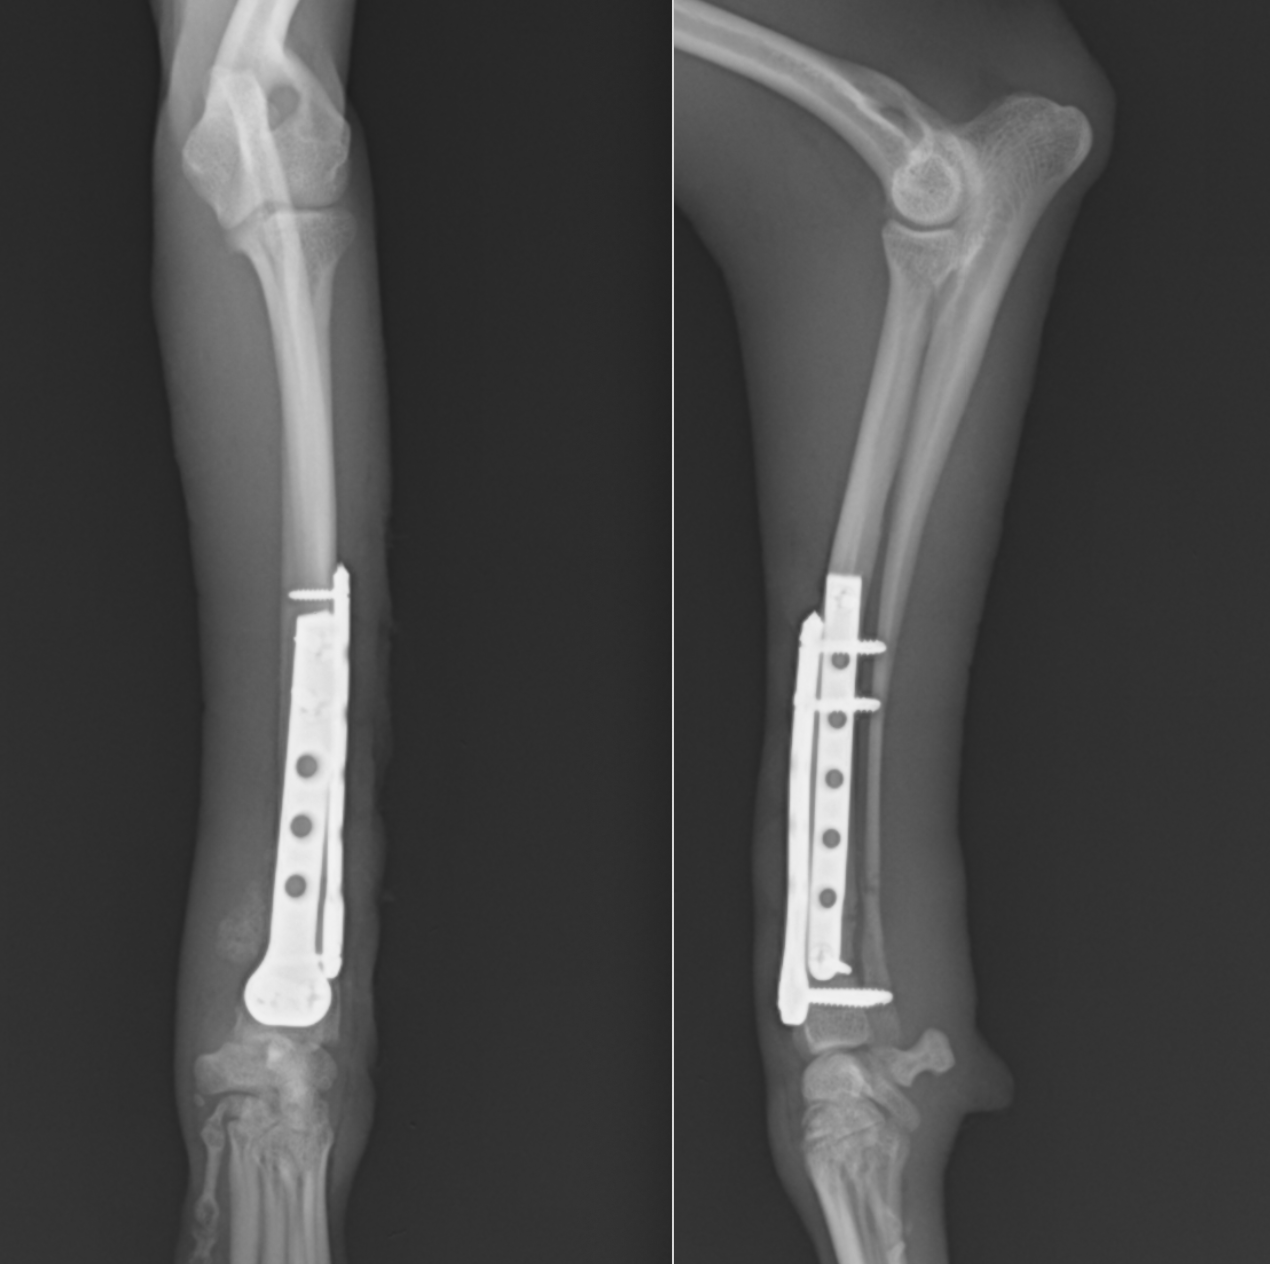

今回の手術後の写真です。非常に長いプレートが入っているのは、手術して再骨折があった場合にはもとのプレートよりも長いプレートを入れる必要があるからです。また、骨が痩せて細くなっているケースが多いので術後も注意が必要です。

術後レントゲンです。橈骨全域に渡ってプレートが入っています。近位は少し外側に曲がっているため、最初からプレートを曲げています。術後2日目には患肢を使っての歩行が可能でした。また、キャスト(ギプス)も使わないので、ストレスなく生活が可能です。術後1ヶ月半ほどで正面のプレートを抜去しています。